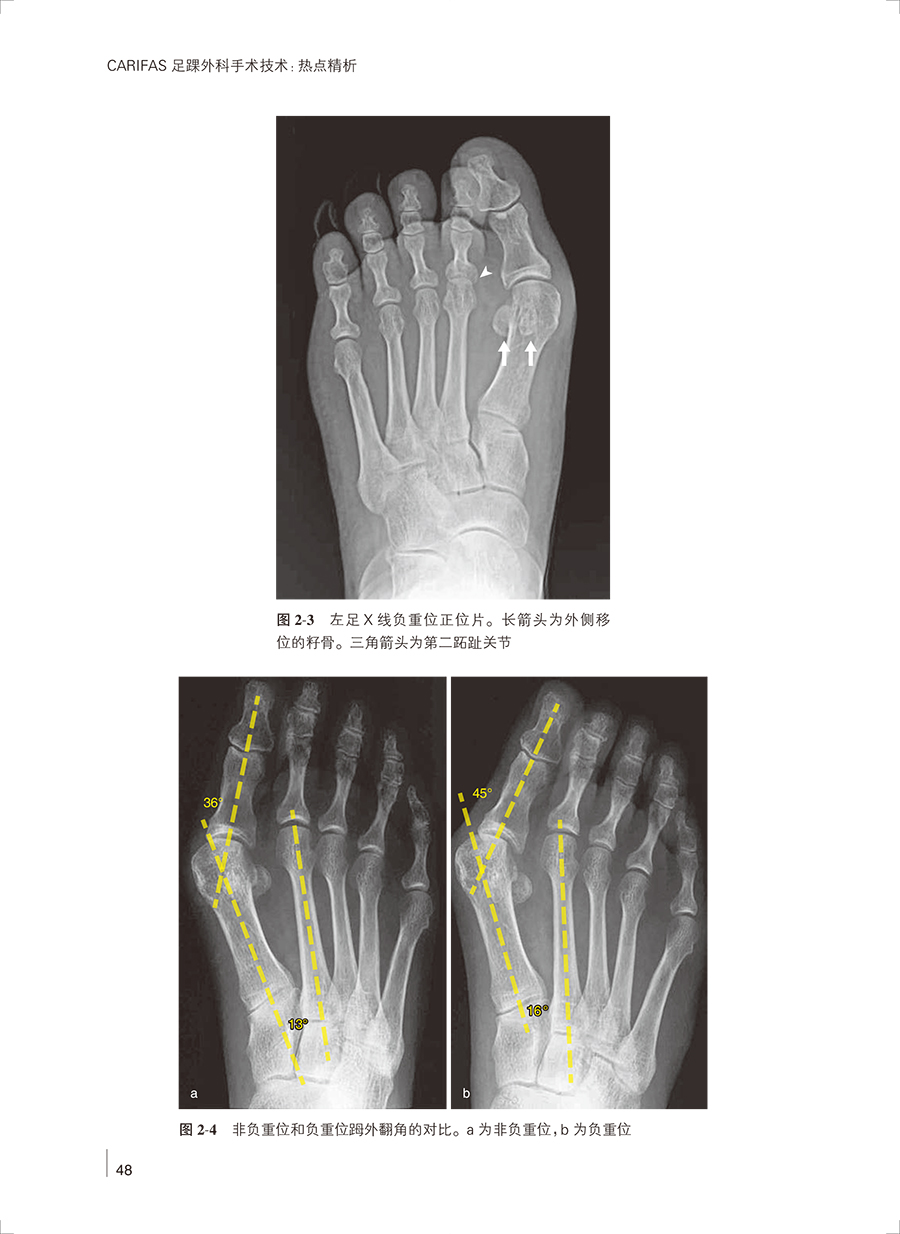

第2 章 外翻的跖骨远端微创截骨术治疗/ 46